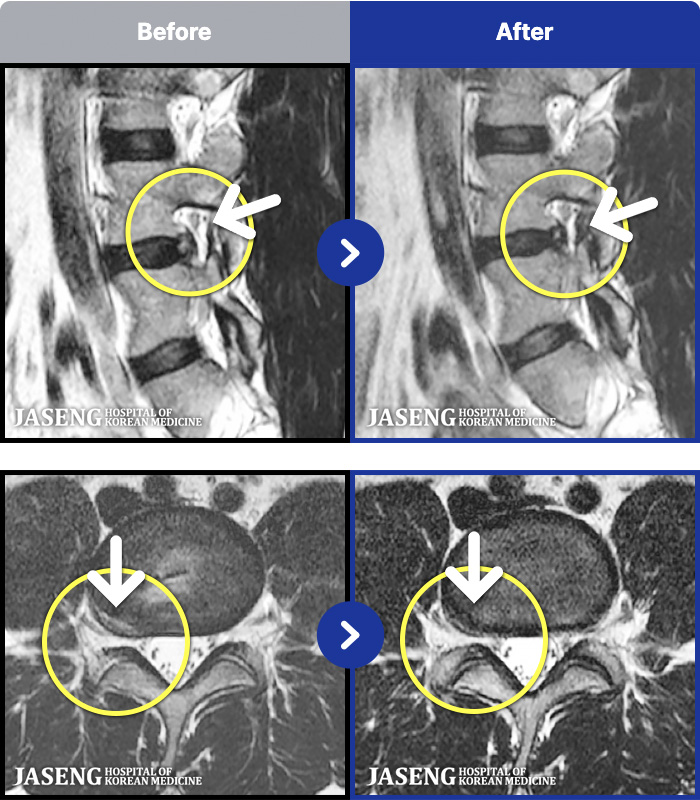

- MRI ġ

MRI ġ

1,296 MRI ũ ʸ Ȯϼ.